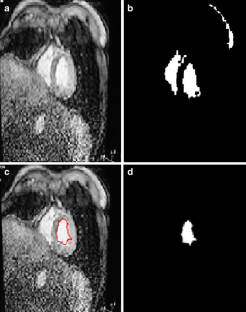

Segmentation of the left ventricle in MRI images is a task with important diagnostic power. Currently, the evaluation of cardiac function involves the global measurement of volumes and ejection fraction. This evaluation requires the segmentation of the left ventricle contour. In this paper, we propose a new method for automatic detection of the endocardial border in cardiac magnetic resonance images, by using a level set segmentation-based approach. To initialize this level set segmentation algorithm, we propose to threshold the original image and to use the binary image obtained as initial mask for the level set segmentation method. For the localization of the left ventricular cavity, used to pose the initial binary mask, we propose an automatic approach to detect this spatial position by the evaluation of a metric indicating object’s roundness. The segmentation process starts by the initialization of the level set algorithm and ended up through a level set segmentation. The validation process is achieved by comparing the segmentation results, obtained by the automated proposed segmentation process, to manual contours traced by tow experts. The database used was containing one automated and two manual segmentations for each sequence of images. This comparison showed good results with an overall average similarity area of 97.89%.

Fig. 1